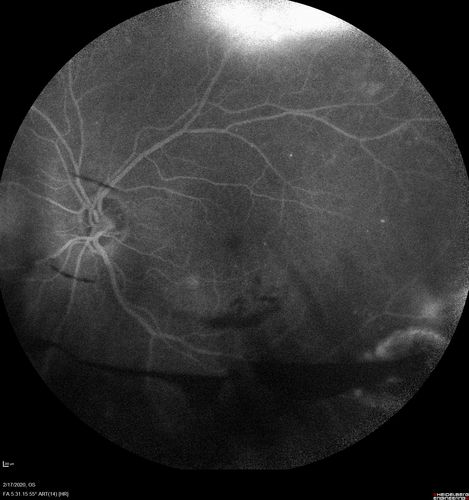

PDR and Vitreous Hemorrhage - High Risk Left Eye - Low Risk Right Eye

50 year old man with type I diabetes mellitus for 26 years. New Vitreous Hemorrhage in the left eye. Both eyes have NVE. Both also have foveal hypoplasia